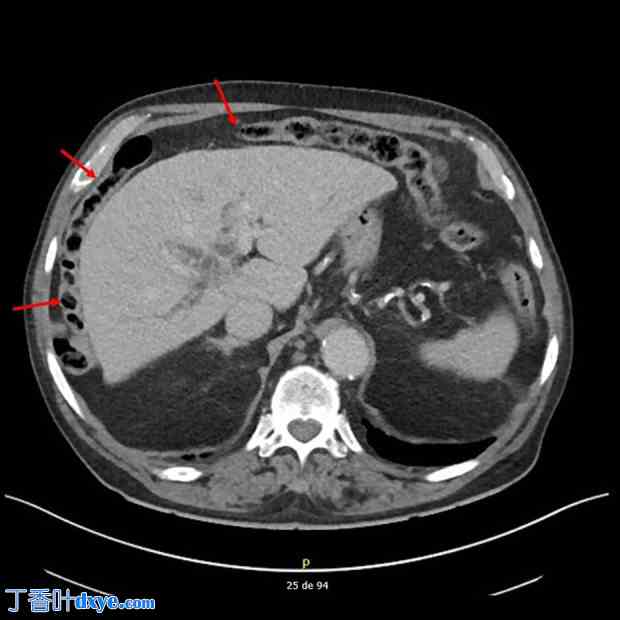

因此,作者不得不采用经皮肝穿刺胆道引流 (PTBD) 的放射学方法,但此举也遇到了一些障碍。患者的结肠明显位于肝脏和横膈膜之间,符合 Chilaiditi 征(图 3);因此,作者实施了联合手术,在腹腔镜下牵拉右结肠,以更好地暴露肝脏和胆道目标。腹膜探查提示肝脏胆汁淤积,并伴有轻微纤维化和硬化前期。将位于肝脏和横膈膜之间的右结肠牵拉至骨盆方向,并用可吸收编织缝线固定右结肠曲。随后可以安全进行 PTBD,然后放置金属胆道支架,手术进行得很顺利(图 4)。在腹腔镜探查过程中,作者发现了一个与肝静脉段相对应的小的白色病变,对其进行了活检以进行病理检查。PTBD 的定位导致胆红素值迅速下降,并提高了患者的舒适度。术后11天,患者出院,在家人的协助和护理下回家。

图3.

图4.

Chilaiditi征:红色箭头指示结肠位于肝脏和右侧膈肌之间。